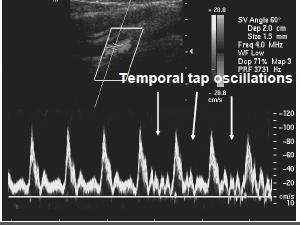

what vessel doe this look like?

what is the sonographer dong to the patient? is this reliable in this vessel?

ECA Temporal Tap can be a useful tool in identifying the ECA, but it is often unreliable. Oscillations can and do occur in the ICA as well. Understanding the anatomical position of the ECA-ICA is the best method.

*fast vibration like taps to get 2-3 in during diastole